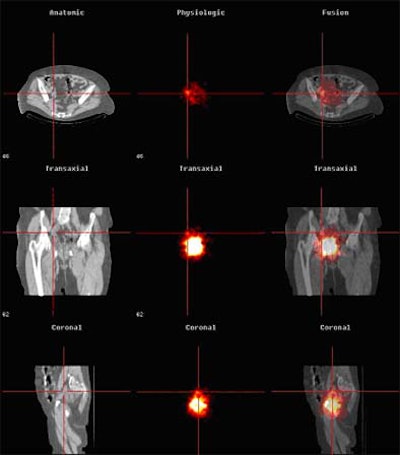

| Above, anatomic (CT, left), physiologic (SPECT, middle) and fused images (right) are seen in a bladder cancer patient with sentinel lymph nodes. Images courtesy of Dr. Amir Sherif. |

The fusion process, while time-consuming, enabled detailed preoperative evaluation, Sherif said. According to the results, 20 sentinel nodes were detected in 5/6 patients, compared to two sentinel nodes in six patients visualized using planar lymphoscintigraphy alone. Five of six metastatic sentinel nodes in invasive bladder cancer were seen using the fusion protocol, while lymphoscintigraphy detected only 1/6 nodes containing metastases.

Overall, planar lymphoscintigraphy alone versus CT-enhanced lymphoscintigraphy detected two and 21 positive nodes, respectively, including 1/2 in patient 1, 0/6 in patient 2, 0/6 in patient 3, 0/4 in patient 4, 1/3 in patient 5, and 0/0 in patient 6, according to the results. Of these, only two positive nodes were detected by the blue dye marker, while the gamma probe detected 10 positive nodes peroperatively. Harvested nodes per patient ranged from six to 24, the total number of detected sentinel nodes per patient ranged from zero to six. All six patients were staged T2.

"The (combined) system is very accurate for localizing the nodes," Sherif said. "Previously we used only planar lymphoscintigraphy with a gamma camera preoperatively, and we had a much lower yield of detected nodes. By using the fused picture with CT/SPECT, we get a much higher yield, first a higher yield of lymph nodes which are considered to be sentinel nodes, and secondly we find anatomical localization (to be) very accurate."